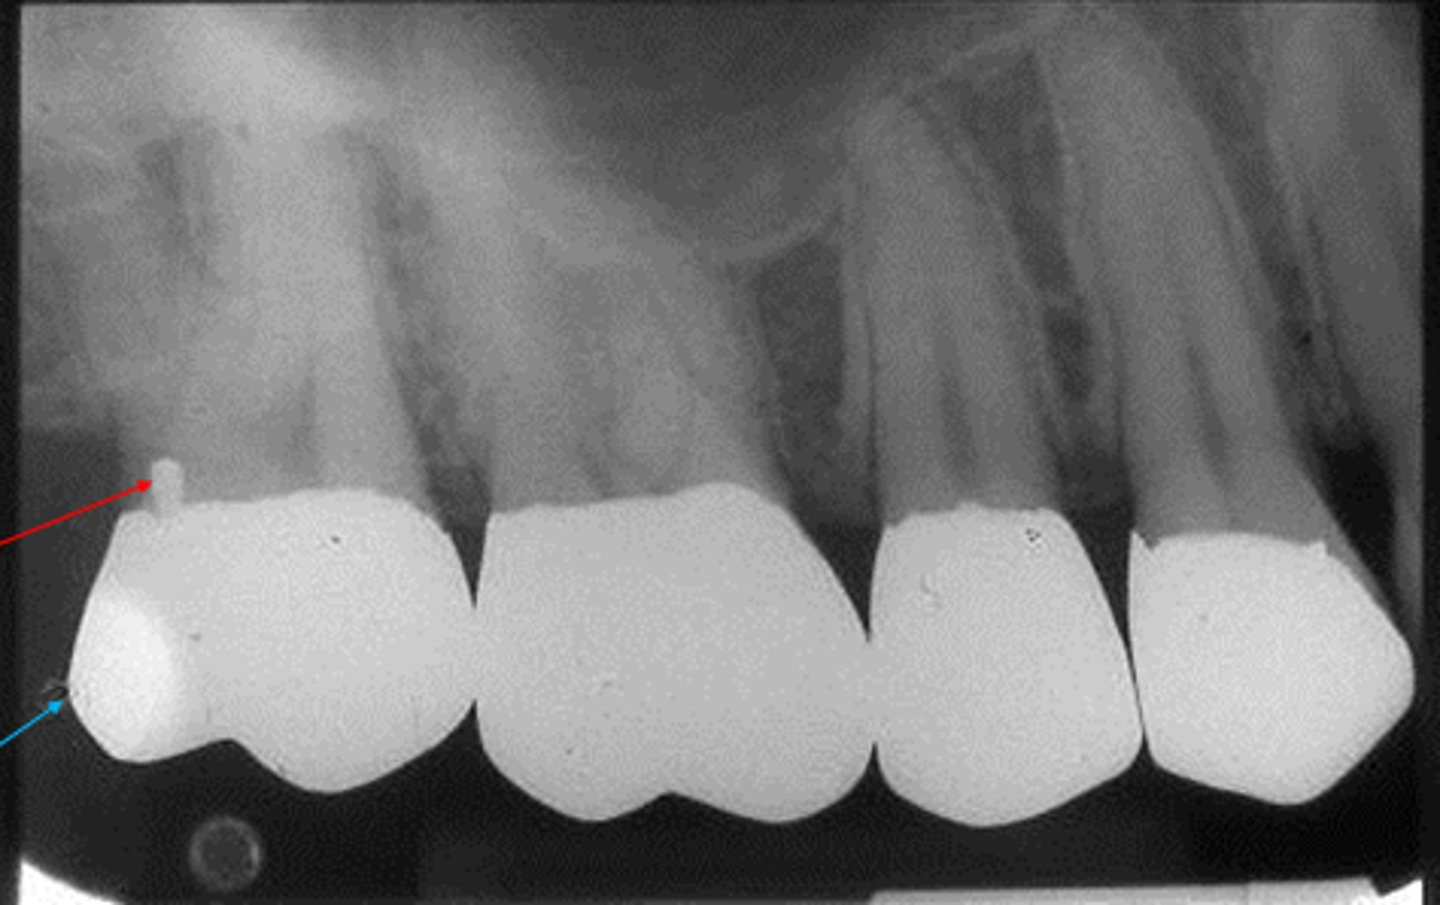

calculus

crown prep

porcelain fused to metal radiograph

porcelain fused to metal image